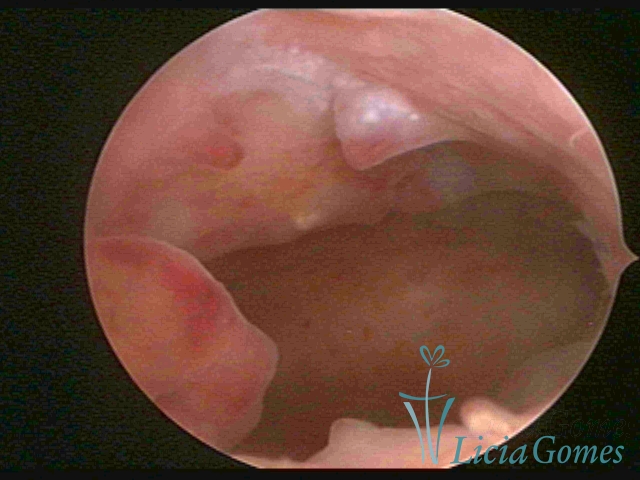

A hipertrofia polipoide é visualizada quando o crescimento endometrial é mais pronunciado, e como o espaço da cavidade uterina é limitado, forma dobras ou sulcos, simulando lesões pseudo polipoides ou polipoides.

A Hiperplasia Complexa tem um aspecto pseudo polipoide, lembrando tecido cerebroide ou com reação deciduoide. A vascularização superficial é mais evidente e com vasos em formatos de saca-rolha ou espirais.